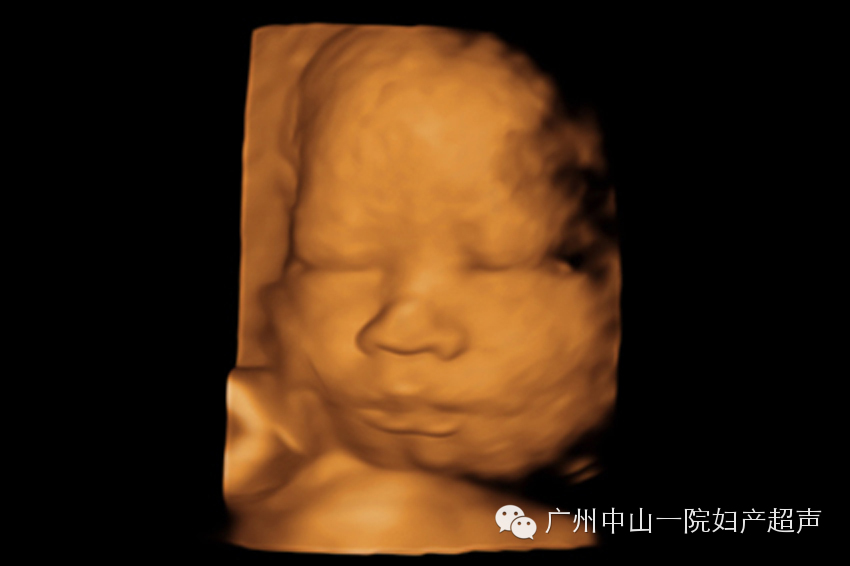

此次检查最重要目的是观察胎儿全身各系统结构是否存在畸形。这个时候,胎儿已经比较大了,三维超声无法获取胎儿的全身照,道理就如同相机无法近距离拍摄大物体的全貌一样。我们通常只建立宝宝的面部三维图像,满足准妈妈们求貌若渴的心情。如果条件良好,宝宝的五官可以清晰的呈现出来,嘴唇、鼻子、眼睛(通常是闭着的)甚至人中都可以一一分辨。对于我来说,工作中最开心的部分就是看着准妈妈们对着宝宝的照片评头论足,感受超声技术的神奇和母子之间的情感交融。